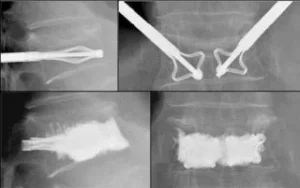

Le fratture vertebrali, se non trattate correttamente, possono portare a gravi complicazioni come dolore cronico, perdita di mobilità, e in alcuni casi, danni permanenti ai nervi. È quindi fondamentale un intervento tempestivo e mirato per ridurre il dolore e favorire la guarigione. I trattamenti per le fratture vertebrali possono includere radiologia interventistica, tecniche minimamente invasive come la vertebroplastica o la kyphoplastica, che permettono di ripristinare la stabilità della vertebra senza ricorrere a interventi chirurgici tradizionali. Queste tecniche vengono eseguite sotto guida radiologica, garantendo alta precisione e riducendo i rischi per il paziente.

In conclusione, le fratture vertebrali sono una condizione comune, che può essere trattata efficacemente con approcci moderni come la radiologia interventistica, che offre un’alternativa sicura ed efficace rispetto alle tradizionali chirurgie invasive. Se sospetti di avere una frattura vertebrale o hai una condizione di salute che aumenta il rischio di fratture, è importante consultare un medico specialista per un’accurata valutazione e per discutere le opzioni di trattamento più adatte.